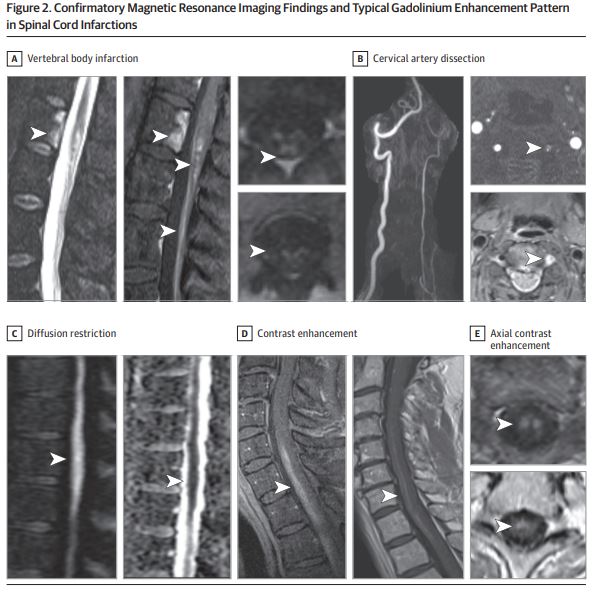

Other common T2-hyperintense patterns are highlighted well in @nzalewski2's paper as shown below.